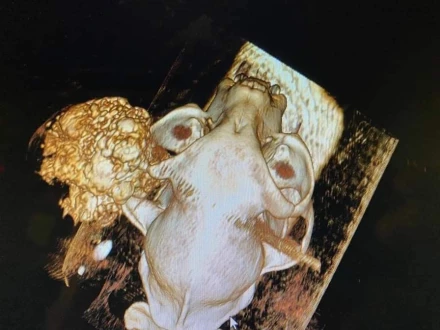

Operacja masywnej zmiany twarzoczaszki